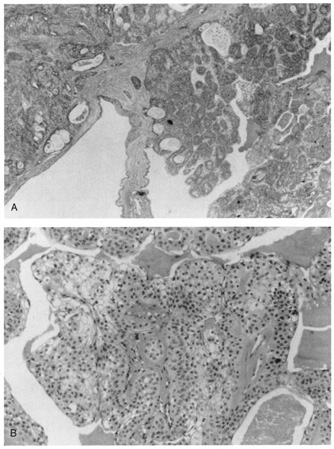

TUMORS Epithelial Tumors The epithelial lining of the lacrimal sac is the same as the rest of the upper respiratory tract (i.e., pseudostratified columnar epithelium). Therefore, tumors are similar to those found elsewhere in the upper respiratory tract, namely papillomas, squamous cell carcinomas, transitional cell carcinomas, and adenocarcinomas. Tumors of the lacrimal sac, however, are relatively rare. They generally cause early symptoms of epiphora, and, upon irrigation, blood may reflux from the punctum. Overlying skin ulceration or telangiectasias may also be associated with lacrimal sac tumors. Papillomas may be squamous, transitional, or adenomatous (Fig. 54). Rarely, a lacrimal sac papilloma may undergo oncocytic metaplasia (i.e., an eosinophilic cystadenoma or oncocytoma). The histology of squamous cell carcinomas is identical to that of those found elsewhere, and these carcinomas are the most common (Fig. 55). Transitional cell carcinomas are composed of transitional cell epithelium showing greater or lesser degrees of differentiation (Fig. 56). Adenocarcinomas are composed of malignant glandular elements. Melanocytic Melanocytic tumors arising from the lacrimal sac are quite rare and are identical histologically to those found in the lid. Mesenchymal The same mesenchymal tumors that involve the lids and orbit may involve the lacrimal sac. |